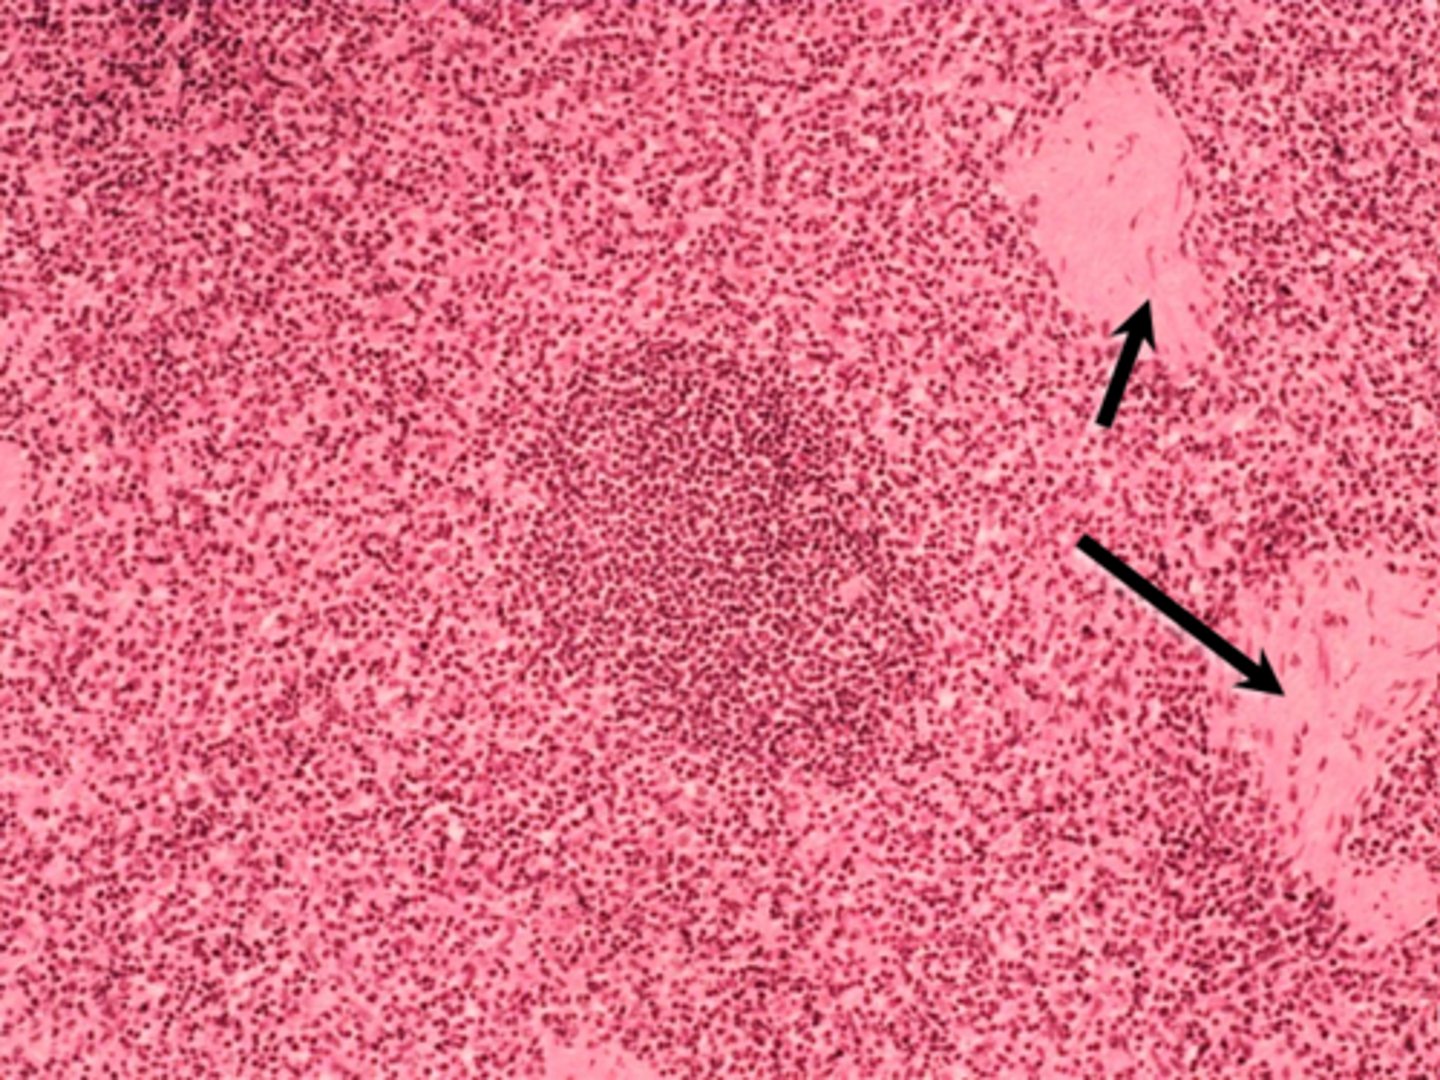

lymph node

cortex & paracortex

ID structure

trabecula

black arrow

lymph node capsule